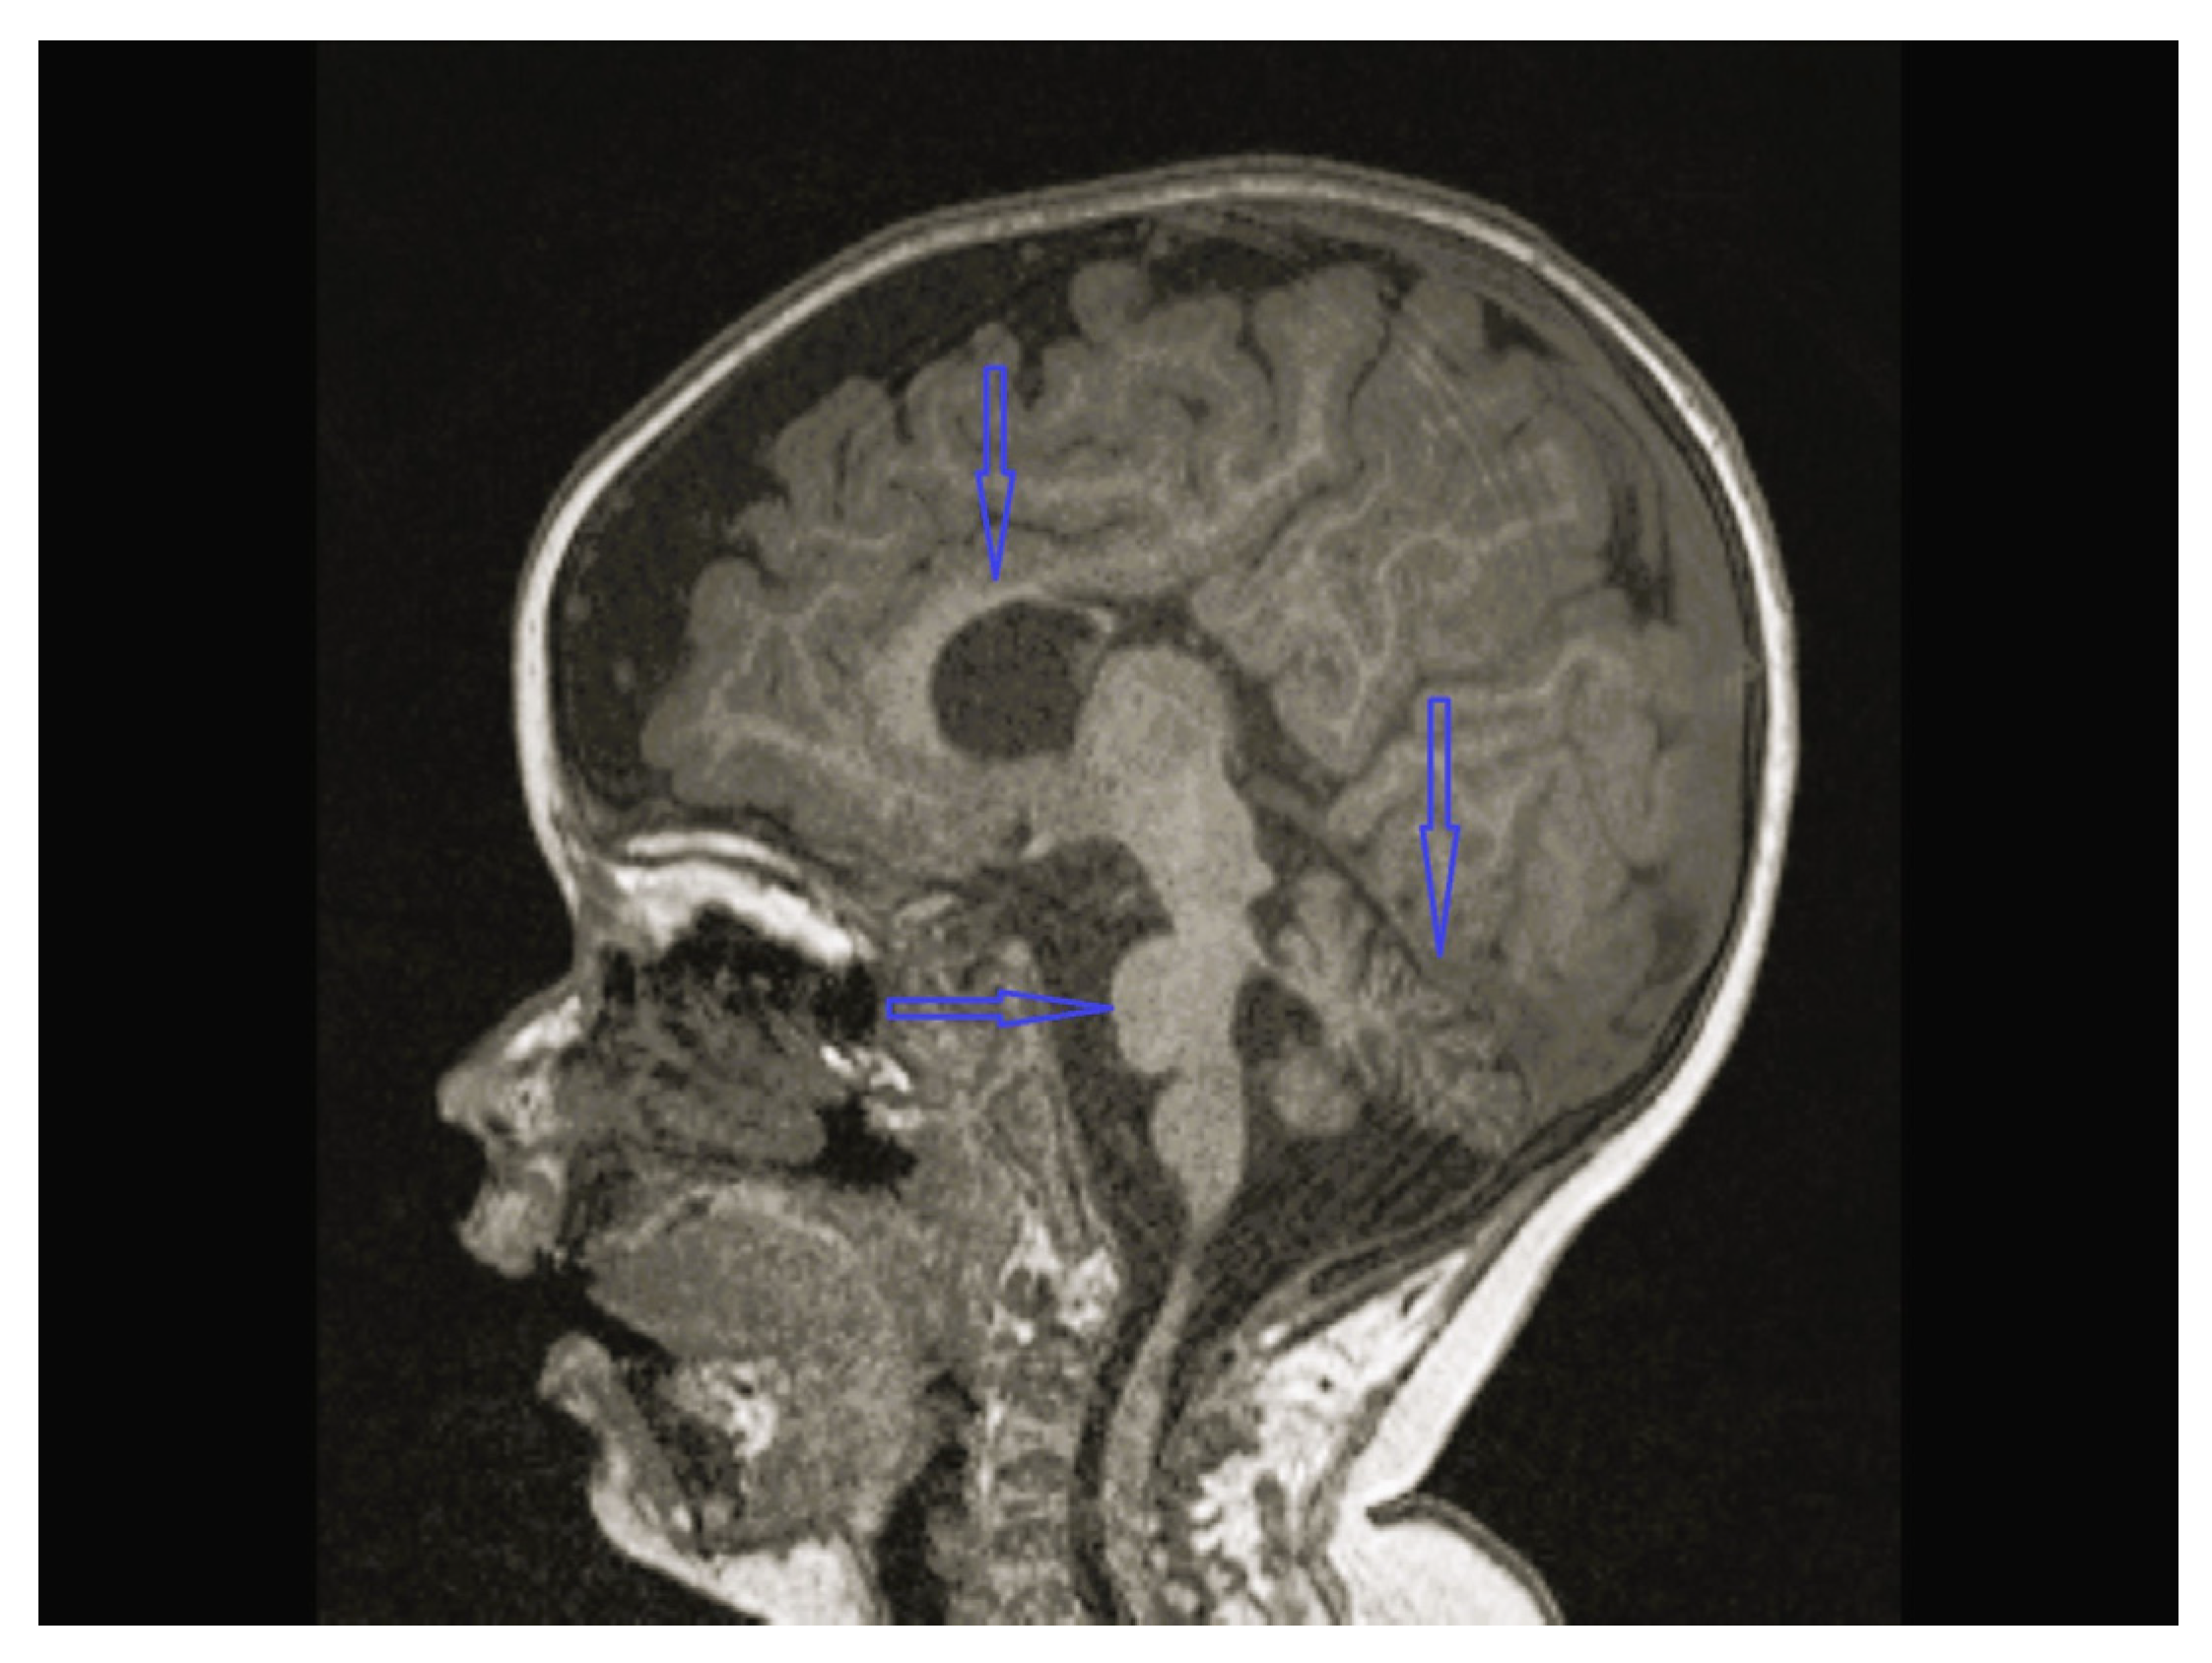

| 1 | - | - | - | Cerebellar hypoplasia, vermis dysplasia and corpus callosum (CC) hypoplasia | Normal | SPG11 c.6730C>T heterozygote (p.L2244F) | Physical therapy |

| 3 | Normal | - | Normal | Vermis and CC hypoplasia | Normal | KIF1A c.773C>T heterozygote (p.V391M) | Physical therapy, baclofen |

| 8 | Normal | - | Multifocal spike and waves pattern | Vermian, CC and brainstem hypoplasia | Normal | KIDINS220 NM_020738.4 c.4388C>A heterozygote p.S1463* | Physical therapy, clonazepam, sodium valproate |